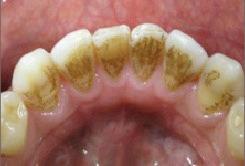

Air polishing technology was first developed in 1945 by Dr Robert Black, originally using aluminium oxide for tooth preparation. In the 1970s, it became popular to remove discolouration using a gentler powder, mainly for use supragingivally. Air polishing was previously seen as a cosmetic treatment, but today it has an important role in pathological treatments, in the form of powder therapy and biofilm removal.

Powder Therapy: A Breakthrough in Biofilm Removal

In the 1990s, the development of biocompatible powders began, and research looked at the potential of air polishing technology to remove biofilm. The development of new powder types and lower-pressure technology enabled both

sub and supragingival treatment, throughout the mouth, making treatment more preventive and pathologically directed. In the late 2000s, subgingival air polishing was introduced as a new treatment modality. The method was initially a revolution in implant maintenance and periimplantitis prevention but has since proven to be highly effective for full mouth debridement – including biofilm removal on gingiva, tongue, mucous membranes, furcations, crowns, bridges and root surfaces. The powder, which consists of amino acids, the body's own protein, is biocompatible and gentle while effectively removing biofilm and light discolouration. The fact that the powder does not contain antiseptics is also an advantage in terms of sustainability and resistance development.